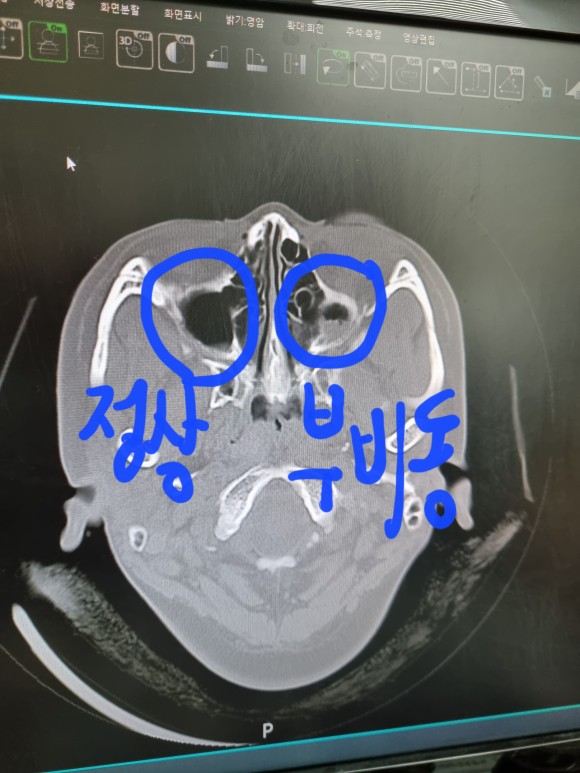

부비강염

하얀 염증(콧물)

부비강염 치료

사진상으로는 아직 절반도 빠지지 않은 염증ㅠㅠ

부비강염

왼쪽에도 약간의 염증이 있지만 정상수준

오른쪽에는 반 이상 하얀 무언가가 가득 찬 그림이 보이시죠?

(새까맣게 비어있는 것이 정상입니다)